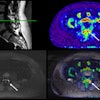

For potential validation, Damestani and colleagues have taken the first step, measuring white matter hemodynamics with spatial specificity in a large, healthy adult cohort. To that end, they produced an FA skeleton, CBF skeleton, and ATT skeleton for every individual in the study.

The researchers used two high-resolution approaches. One is a technique called multidelay pseudocontinuous arterial spin labeling (md-pCASL), or labeling blood at the level of the neck and allowing the blood to perfuse to different regions of the brain, allowing different post-labeling delay times, with a series of times allowed for the perfusion to take place. When they subtracted the labeled and unlabeled images and applied a quantification process, they were able to extract the CBF measure. Multidelay pCASL also quantified the ATT or the time taken for blood to reach the brain tissue from the labeling plane.

The other technique using 3-tesla diffusion imaging produced 1.5 millimeter (mm) isotropic resolution.

Damestani and colleagues developed their quantification approach for CBF and ATT in-house and then projected the corresponding maps onto the white matter skeletons.

The framework for this study complemented gray matter studies by identifying the relationship between white matter hemodynamics and age and sex. Damestani said the team mapped CBF and ATT on average across the entire cohort within white matter, with the spatial specificity they were looking for.